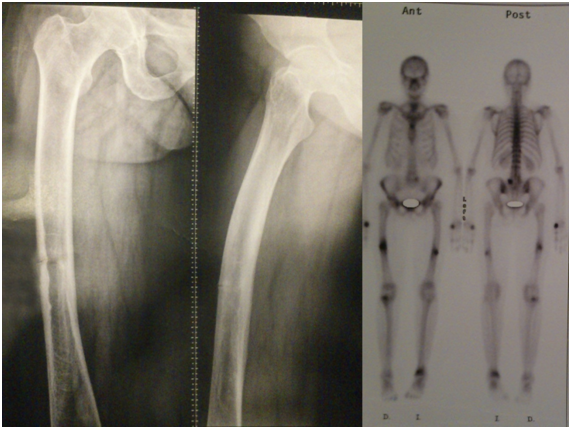

The consolidation of the right femur was completed at 11 months, no longer had pain or discomfort in the femur but continued with pain in the left thigh, new radiographs were made showing hypertrophic pseudoarthrosis so it was decided to perform a new surgery and place a plate blocked with minimally invasive technique on the nail, with this procedure immediate pain relief is achieved, full load was allowed after 2 weeks and consolidation was achieved 3 months later (Figure 4). Currently, the patient is 2.5 years old and does not present any pain or limitation in hip and knee mobility (Figure 5).

Figure 5 Consolidated fractures, 2 years post surgery.